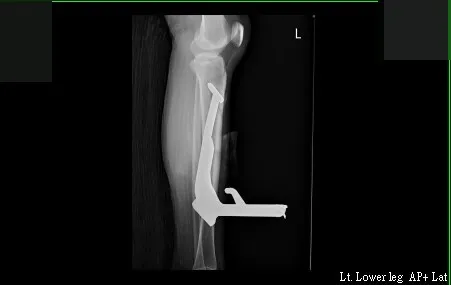

收治李小姐的高雄市立大同醫院整形外科主任賴雅薇表示,李小姐到院馬上被送進開刀房,在X光片下,可看到尾部有倒勾、長達23公分的中柱,整隻插在李小姐的左腿裡,「整個開刀房人員都圍過來看」。

在X光片影像中,可看到長達23公分的中柱,直直插在李小姐左腿裡。讀者提供